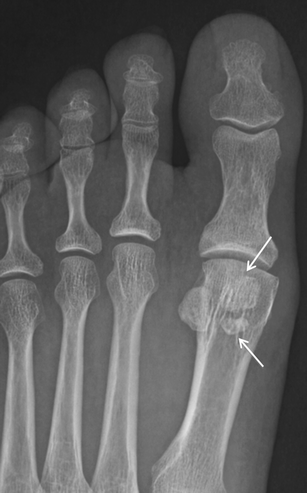

Sesamoid Bone X Ray Collection 2022 Sesamoid Bone X Ray Collection 2022

Sesamoid Bone X Ray

Sesamoid fracture | Radiology Reference Article | Radiopaedia.org Radiology Review - Sesamoid fracture | Axis Sports Med Toes (sesamoid view) | Radiology Reference Article | Radiopaedia.org Sesamoid | Radiology Reference Article | Radiopaedia.org Sesamoid bone - Wikipedia Sesamoid Bone X Ray